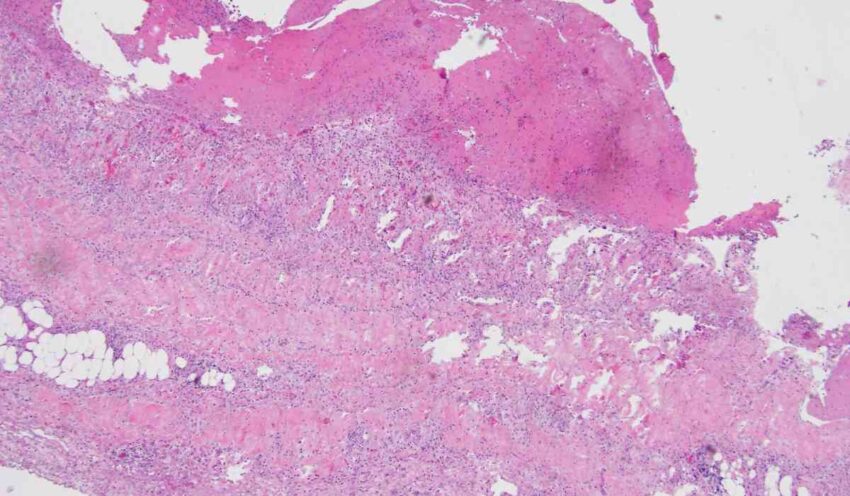

The bullous pemphigoid market comprises autoimmune skin condition characterized by formation of fluid-filled blisters on the skin. Bullous pemphigoid treatment involves medication like corticosteroids, immunosuppressants and biologics to reduce symptoms of itching and blistering.